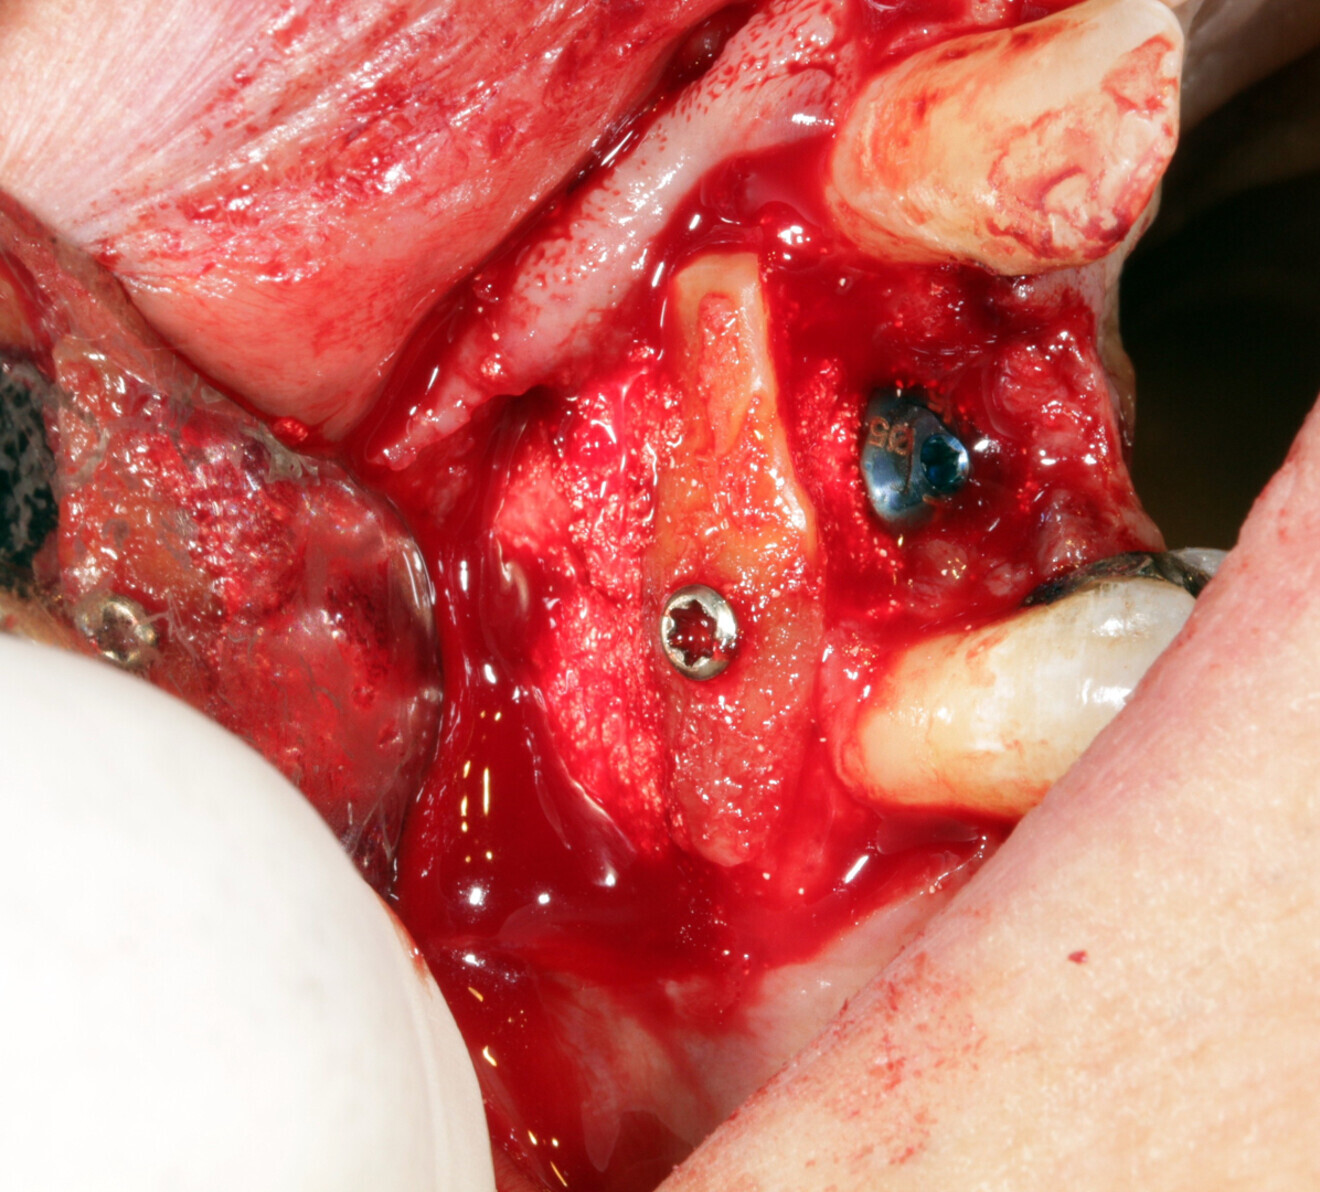

A 55-year-old patient with a radicular fracture at tooth #13 under a crown and a fistula opposite was treated (Fig. 15). The plan was to treat this patient with simultaneous extraction, implantation and aesthetic restoration. Unfortunately, as sometimes happens and despite the precautions taken, a large part of the vestibular wall of the alveolus was extracted with the root, creating a significant bone defect. A full-thickness flap was elevated and the implant placed. The root was prepared and fixated with an osteosynthesis screw to replace the lost wall (Fig. 16). The space between the root and the implant was filled with a hydroxyapatite-based biomaterial (Fig. 17). This bone reconstruction was combined with a connective graft. The flap was stretched and sutured with a #5/0 resorbable braided thread (Fig. 18). An impression was taken and a temporary screw-retained prosthesis was made during the day by the laboratory and fitted the same evening. The sutures were removed on the tenth day. The temporary prosthesis was removed after two months to check that the implant had been successfully integrated into the bone. The osteosynthesis screw was visible under the gingiva and was removed after six months (Figs. 19 & 20). A CBCT assessment was performed at the same time. The radicular graft had ankylosed perfectly and the ridge regenerated ad integrum. The definitive prosthesis was fitted by our colleague (Fig. 21).

Fig. 16: Preparation of the root and fixation with an osteosynthesis screw to replace the lost wall.

Fig. 17: The space between the root and the implant was filled with a hydroxyapatite-based biomaterial.